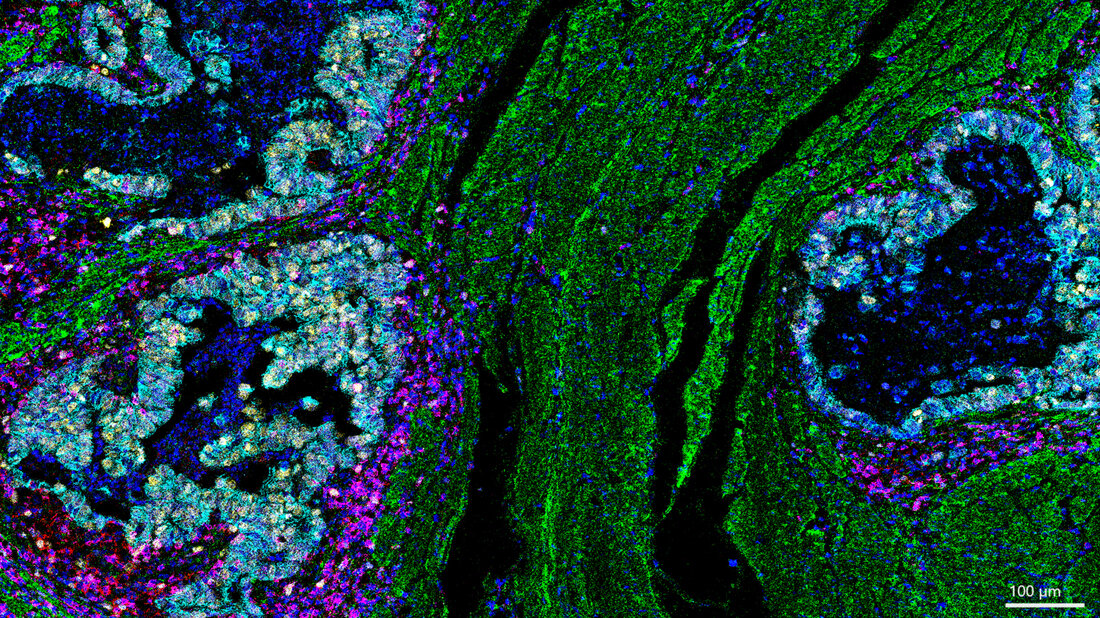

„Unsere Daten zeigen, dass die Reaktion des Immunsystems entscheidend mitbestimmt, wie gut eine Therapie wirkt – selbst wenn der Tumor sich genetisch kaum verändert“, sagt Co-Studienleiter Prof. Dr. Michael Quante, Leiter des Zentrums Gastrointestinale Tumore der Klinik für Innere Medizin II am Universitätsklinikum Freiburg. Für die Studie wurden Gewebeproben von 27 Patientinnen und Patienten mit lokal fortgeschrittenem Speiseröhrenkrebs untersucht. Alle hatten eine sogenannte neoadjuvante Therapie erhalten – also eine Behandlung vor der Operation, meist in Form einer Chemotherapie oder kombinierten Strahlen-Chemotherapie. Dabei zeigte sich: Die Krebszellen selbst blieben erstaunlich stabil. Die Veränderungen fanden vor allem im Umfeld des Tumors statt – in den Immunzellen, dem Bindegewebe und den Signalwegen zwischen Zellen.

Besonders auffällig war: In Tumoren, die schlecht auf die Therapie ansprachen, fanden die Forscherinnen und Forscher Hinweise auf eine sogenannte Immunflucht. Dabei verändere der Krebs bestimmte Oberflächenmerkmale, um vom Immunsystem nicht mehr erkannt zu werden. Auch hemmende Signale wie das Molekül PD-L1 seien bei diesen Patientinnen und Patienten erhöht gewesen. Diese Signale gelten als mögliche Ziele für moderne Immuntherapien. Die Untersuchung wurde im Rahmen der MEMORI-Studie durchgeführt, an der mehrere Standorte des Deutschen Konsortium für Translationale Krebsforschung (DKTK) beteiligt waren – darunter München, Freiburg und Essen. Eine zentrale Komponente der Studie war die Analyse der Tumorevolution unter Therapie mittels Gensequenzierung, die zusammen mit Co-Studienleiter Prof. Trevor Graham, Direktor des Centre for Evolution and Cancer am Institute of Cancer Research in London, im Rahmen eines Krebshilfe Mildret Scheel Stipendiums für Dr. Melissa Barroux durchgeführt wurde.